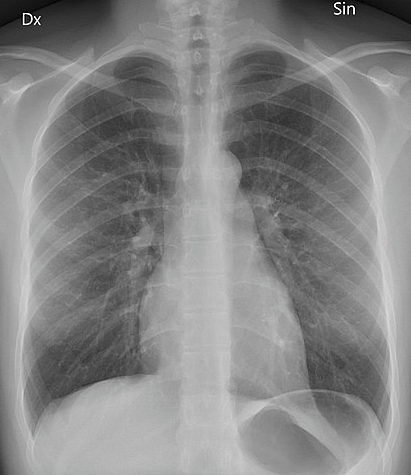

Auf einem Röntgenbild erscheinen die Knochen als helle/weiße Bereiche, während die Luft als schwarze oder dunklere Bereiche erscheint. Der andere hellere Bereich in der Mitte des Bildes ist das Herz. Der Muskel, aus dem das Herz besteht, ist ebenfalls sehr dicht und verhindert, dass Röntgenstrahlen hindurchdringen.

Posteroanteriores Röntgenbild der Brust

Von Mikael Häggström (Eigenes Werk) via Wikimedia Commons